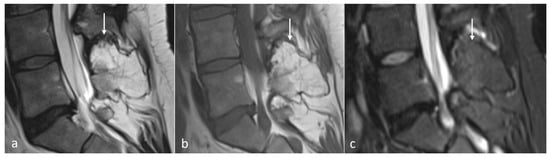

The typical imaging appearance is a well-circumscribed lytic lesion. They can occasionally be expansile and also sclerotic (Figure 6a–c). On MRI, the lesions typically appear as a T1 and T2 hypointense mass, which shows high signal on T2 STIR or T2 fat-saturated images. The lesions enhance after contrast administration [27].

Figure 6.

Sagittal T1 (a), T2 (b) and CT (c) images of a sclerotic myelomatous deposit involving a thoracic spinous process (white arrows). While myeloma typically tends to present as lytic lesions, occasionally they can be expansile and sclerotic as seen here.